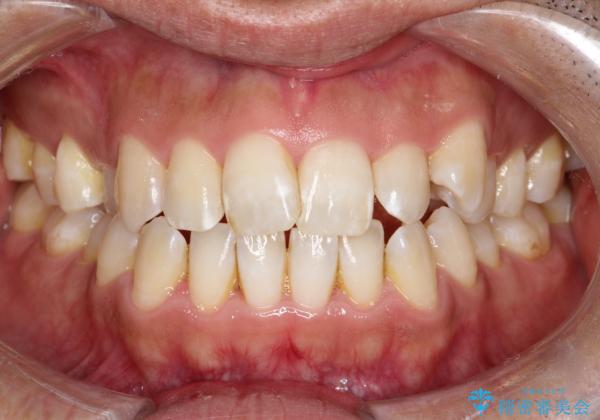

目立たない矯正で八重歯を改善

- 左上の八重歯を気にされて来院されました。精密な検査の結果、歯列全体を広げながら八重歯を奥へ移動させることで、美しい歯並びと機能的な咬み合わせが得られると診断。患者様のご希望に合わせ、透明で目立ちにくい**インビザライン(マウスピース矯正)**による治療計画を立案しました。抜歯を避け、歯を少しずつ遠心(奥)へ移動させることで、歯が並ぶスペースを確保し、叢生(歯のデコボコ)を改善します。

今回の矯正治療では、透明なマウスピース型の装置インビザラインを使用しました。この装置は目立ちにくく、取り外しが可能なため、食事や歯磨きも普段通りに行えます。遠心移動という方法で奥歯を後方に動かし、前歯を並べるためのスペースを確保。これにより、抜歯することなく、左上の八重歯を含む叢生を効果的に改善し、整った美しい歯並びと良好な咬み合わせを獲得していただけました。